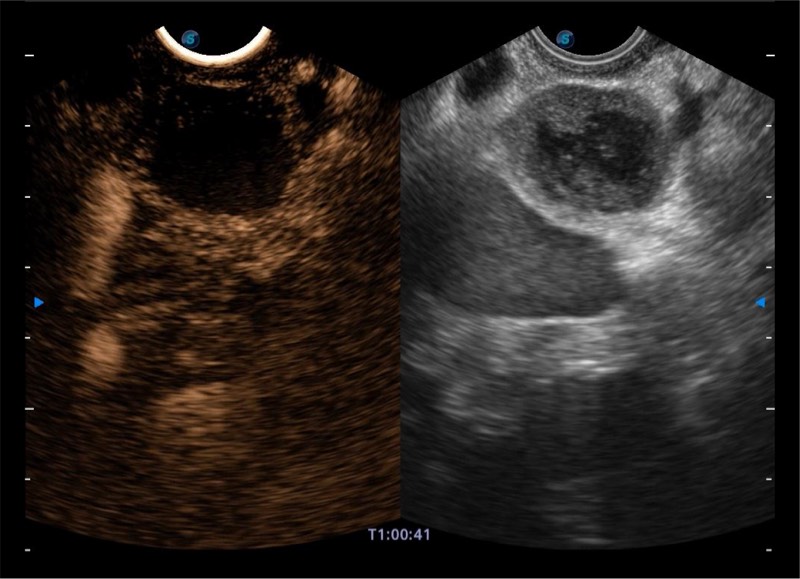

• 搭载百万级CMOS成像技术

• 及自主研发凸阵换能器,

• 可呈现优质的内镜和超声画面

基于二十年的超声技术积累,球速体育入口提供了最新一代的独立超声主机,在提供高质量图像的同时满足多学科使用。具备常见多普勒技术并提供弹性成像、声学造影等高端影像技术。新一代传感器具有更强的抗干扰能力并减少图像伪影。